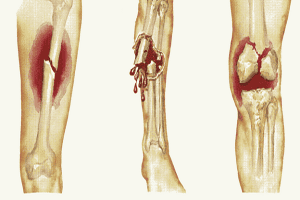

Gãy xương cành tươi là một loại gãy xương mà xương chịu lực uốn cong dẫn tới nứt gãy. Áp lực gây ra sự gãy xương không tách nó thành từng phần. Gãy xương cành tươi thường được gọi là gãy xương một phần hoặc không hoàn toàn, chỉ gãy một phần ở thân xương trong đó vỏ xương một bên bị gián đoạn, bên còn lại vỏ xương vẫn còn nguyên.

Gãy xương cành tươi thường gặp ở cẳng tay, khi xương cong trước khi gãy và màng ngoài xương chưa đứt rời. Gãy cành tươi nằm bên trong màng ngoài xương. Gãy xương cành tươi có thể rất khó chẩn đoán do trẻ nhỏ vẫn có thể sử dụng chi bị ảnh hưởng một cách bình thường. Dạng gãy xương này thường bị nhầm lẫn với bầm tím hoặc bong gân.

4. Biến chứng gãy xương cành tươi

Gãy xương kiểu cành tươi rất khó nhận biết ở trẻ em. Nếu không được điều trị sớm có thể gây ra một số biến chứng bao gồm:

- Tổn thương bất kỳ dây thần kinh hoặc mạch máu xung quanh vị trí chấn thương

- Chảy máu bất ngờ

- Biến dạng chi trong quá trình lành xương

Ngoài ra, nếu không được điều trị đúng cách gãy xương cành tươi có thể chuyển sang gãy xương hoàn toàn, và để lại biến chứng nguy hiểm hơn như: Chèn ép khoang, liệt thần kinh, vẹo trục, viêm xương, di lệch xương, biến dạng chi,...